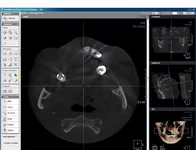

Хотя увы прошло 6 лет и имею рецедив там где зуб сохранили, опять киста и еще одна тоже в процессе образования, просто ппц блин вроде снимки показывают что качественно каналы запломбированы, толи материал херовый был толи особенность такая анатомическая.